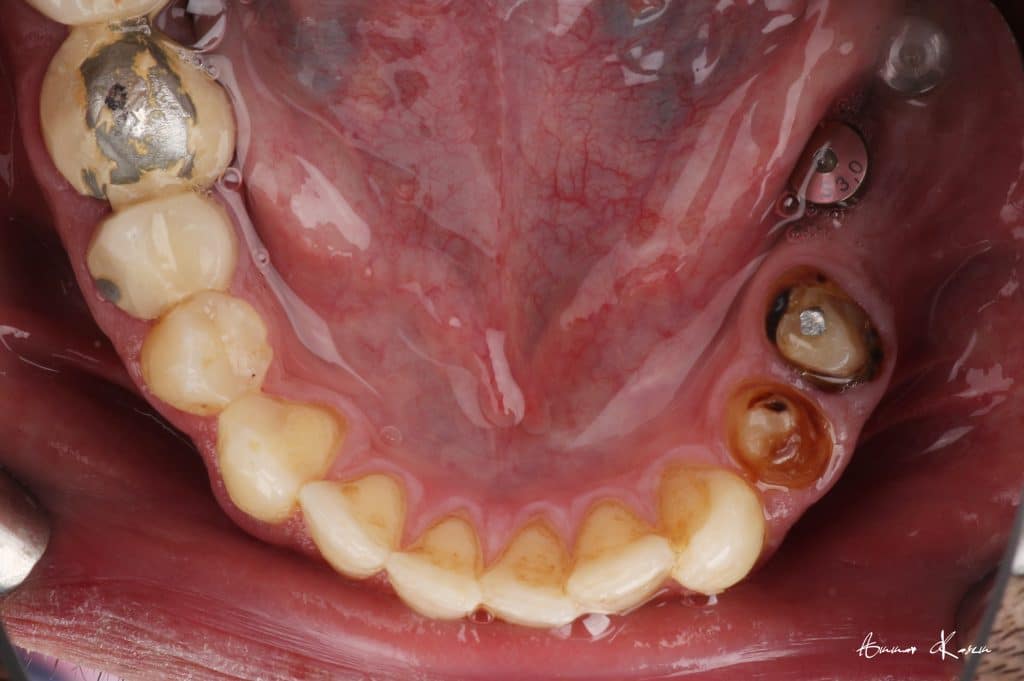

35 years old male patient having old PFM restorations

The patient was normally class I occlusion type ( according to old photos and cephalometric analysis) till he received this defective restorations 10 years ago

With time, the mandible shifted till become habitual class III

1- Removal of old restorations